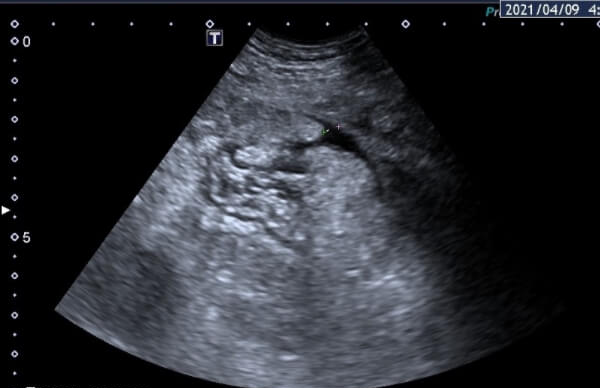

卵巢过度刺激是一种潜在的并发症,通常发生在进行辅助生殖技术(如试管婴儿)的女性身上。这种过度刺激可能会引起卵巢肿胀、卵巢腹水、卵巢疼痛等症状。但是,对于做试管婴儿的患者来说,卵巢过度刺激是否会影响移植的成功率,还要从多个方面判断。

在卵巢过度刺激综合征(OHSS)的情况下,尤其是存在腹水和胸水的情况下,如果患者盲目进行胚胎移植,那么可能会增加移植的风险,比如移植失败,或是对身体造成较大的伤害,这通常是不利于试管移植成功的。

如果在试管移植前存在卵巢过度刺激综合征,且还存在电解质失衡、腹水等并发症的情况下,反而盲目进行胚胎移植,那么可能会降低试管移植的成功率。从而导致试管移植的失败。